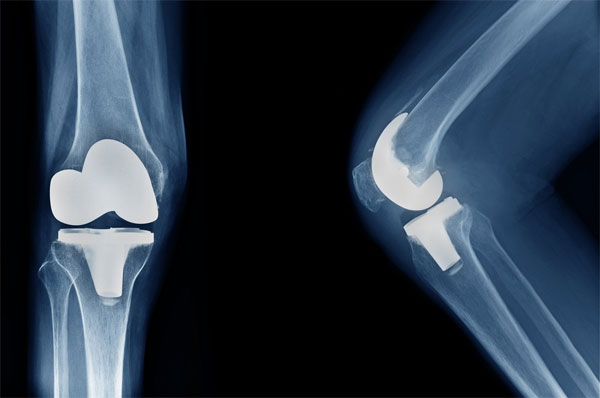

Revision arthroplasty — a surgery performed when an artificial hip or knee joint wears out, loosens, or fails — is becoming more common as implants installed 15–20 years ago begin to reach the end of their lifespan. Artificial joints typically last only 20–25 years, making wear and tear inevitable.

Prof Vijay Kumar of AIIMS noted that the surge in degenerative arthritis cases over the past two decades led to a substantial number of joint replacements in elderly patients, many of which now